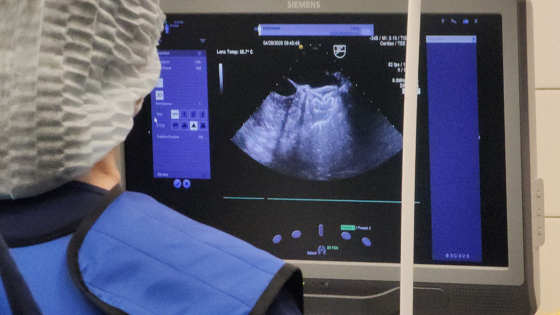

В Кузбассе выполнили операцию, которых в России проводят не более 500 в год. Она потребовалась 51-летнему жителю Осинников.

Мужчина страдал от аритмии и склонности к образованию тромбов, однако кроворазжижающие препараты ему были противопоказаны. Это с большой вероятностью могло привести к инсульту. Тогда было решено провести хирургическое вмешательство.

«‎Чтобы избежать сосудистой катастрофы, пациенту провели редкую операцию – имплантировали окклюдер ушка левого предсердия», – рассказал 5 мая министр здравоохранения Кузбасса Денис Беглов в своем Telegram-канале.

Устройство не позволит образовываться тромбам, что сохранит здоровье мужчины.

В Минздраве отметили, что вмешательство провели малоинвазивным методом, что позволило пациенту быстро пойти на поправку.